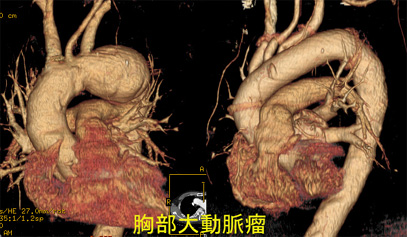

| 胸部大動脈手術 | 18 | 20 | 19 | 22 | 29 | |

| 急性A型解離 | 7 | 8 | 7 | 5 | 12 | |